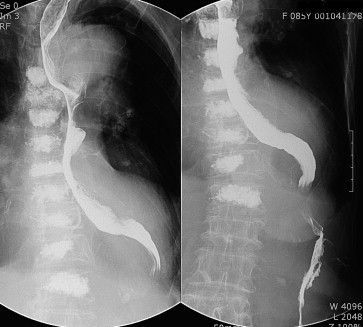

Dilation of aorta can lead to mechanical compression of the esophagus leading to dysphagia. This condition is known as dysphagia aortica. The risk factors of dysphagia aortica are: - Hypertension - Women with short stature - Kyphosis - Thoracic aortic aneurysm The management of dysphagia aortica is conservative as well as surgical. If cardiovascular disorder is causing dysphagia, it is imperative to alleviate underlying cardiovascular disease. Reference: https://www.sciencedirect.com/science/article/pii/S1873959811001013 Image via: https://www.ncbi.nlm.nih.gov/pmc/articles/PMC4268299/#:~:text=Dysphagia%20aortica%20is%20a%20difficulty,stature%2C%20hypertension%2C%20and%20kyphosis.